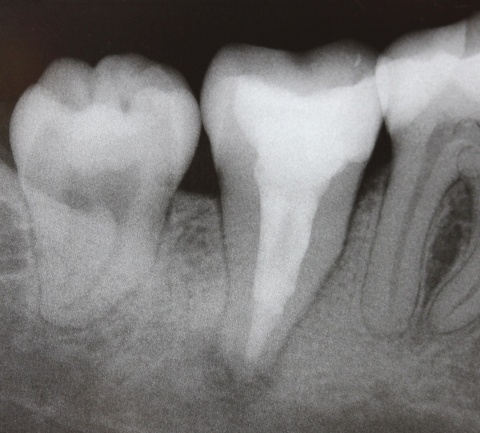

Ein nach Applikation des MTA angefertigtes Kontrollbild zeigt den suffizienten apikalen Verschluss der Konstriktion in einer Schichtstärke von etwa vier Millimeter (Abb. 2). Gleichzeitig wird in der Aufnahme die ausgedehnte Kanalstruktur des Zahnes 47 deutlich.

Im zweiten Schritt wurde durch plastisch erwärmte Guttapercha im Sinne der Back-Fill-Phase das Kanalsystem vollständig gefüllt und der Zahn anschließendadhäsiv verschlossen (Abb. 3). Zwölf Monate nach der Revisionsbehandlung ist die Patientin weiterhin beschwerdefrei und die Kontrollaufnahme zeigt den deutlichen Rückgang der apikalen Osteolyse (Abb. 4).